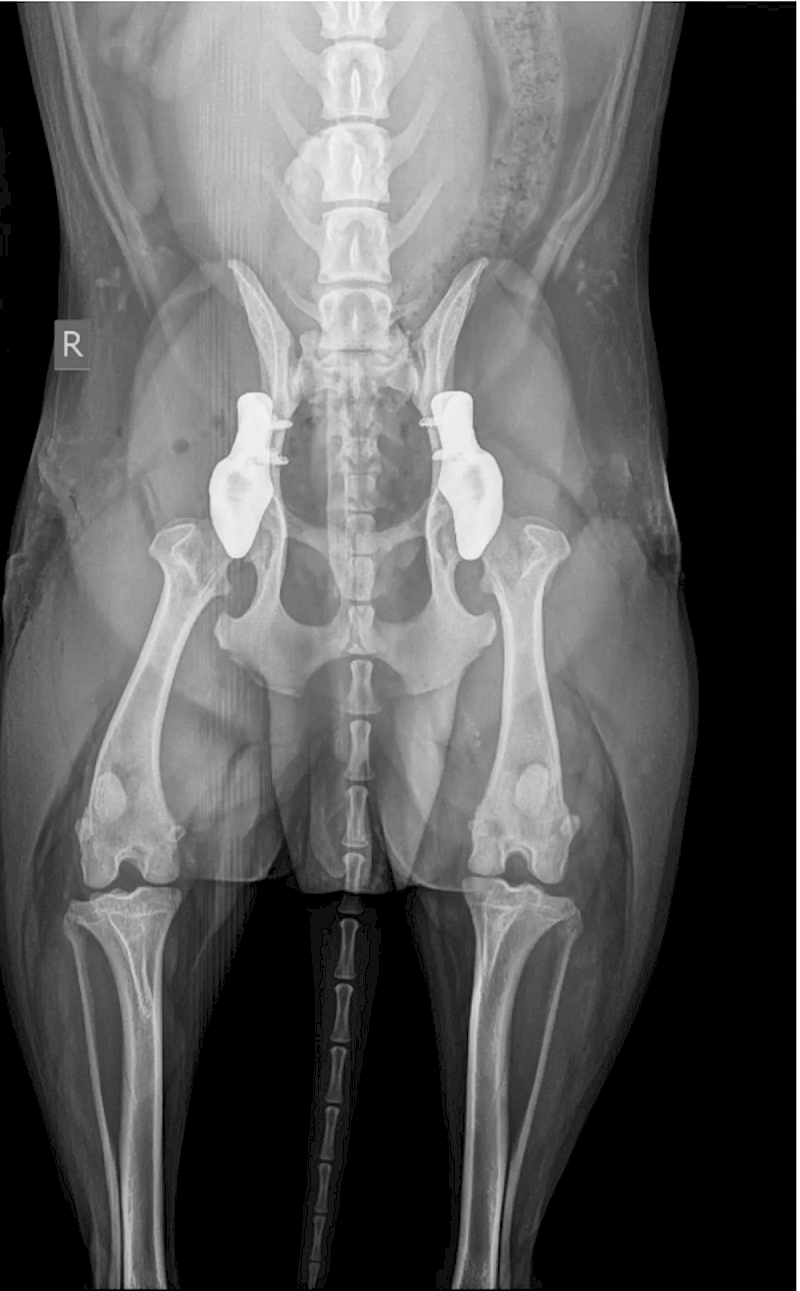

Radiographie avant l'opération du beagle Mauro

Une équipe de deux vétérinaires orthopédistes a implanté deux prothèses de hanche sur mesure imprimées en titane 3D chez un chien. Mauro, un beagle d’environ 20 kg, souffrait d’une dysplasie sévère de la hanche.

Mauro avait des difficultés à marcher et à se lever. Il ne supportait pas les longues promenades. Fin octobre dernier, il a été examiné au AniCura Dierenartsencentrum Herckenrode à Hasselt.